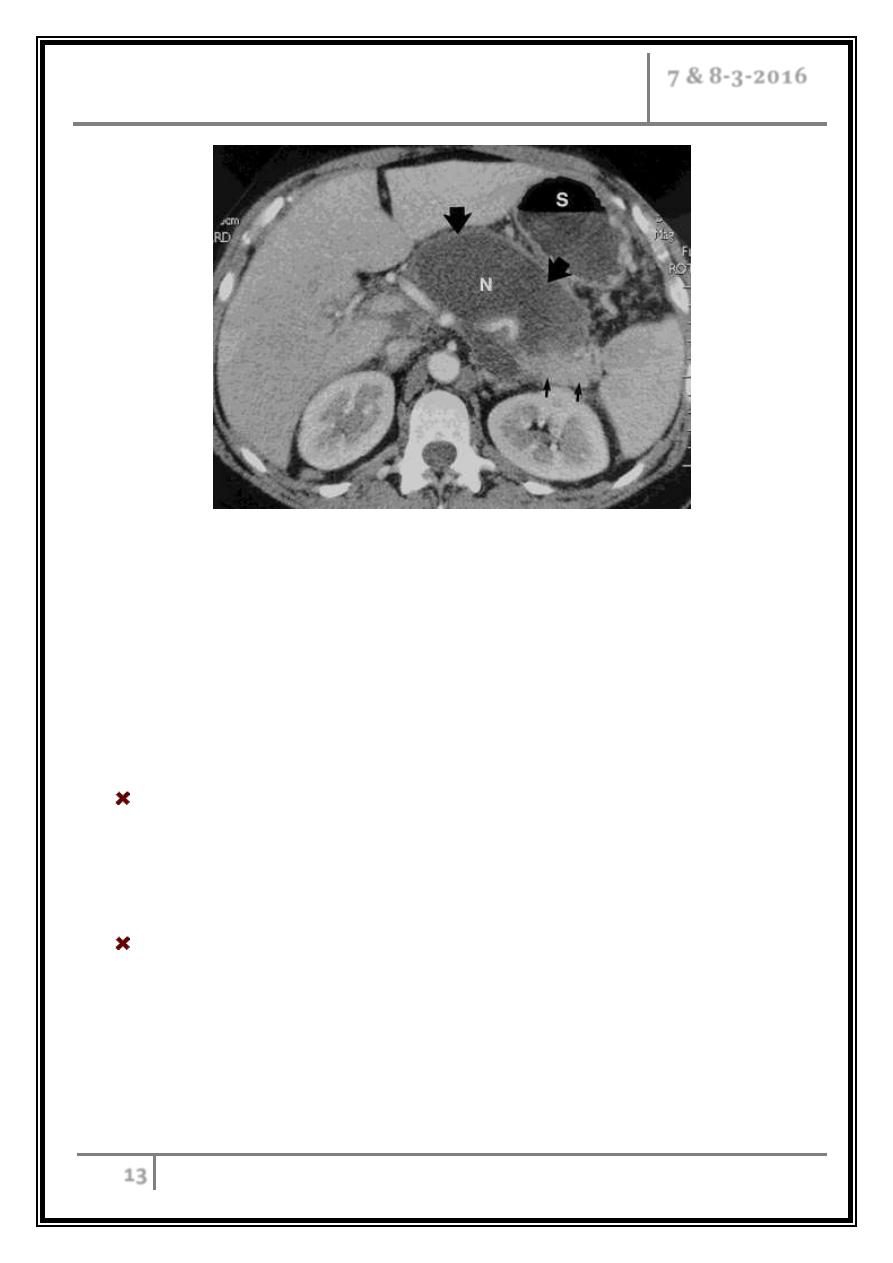

50 year-old woman with acute pancreatitis (1st view)

(a, b) Transverse CT scans obtained with intravenous and oral contrast

material reveal an encapsulated fluid collection associated with liquefied

necrosis (large straight arrows) in the body of the pancreas. The head, part of

the body, and the tail of the pancreas are still enhancing (small straight

arrows). N = liquefied gland necrosis, S = stomach.